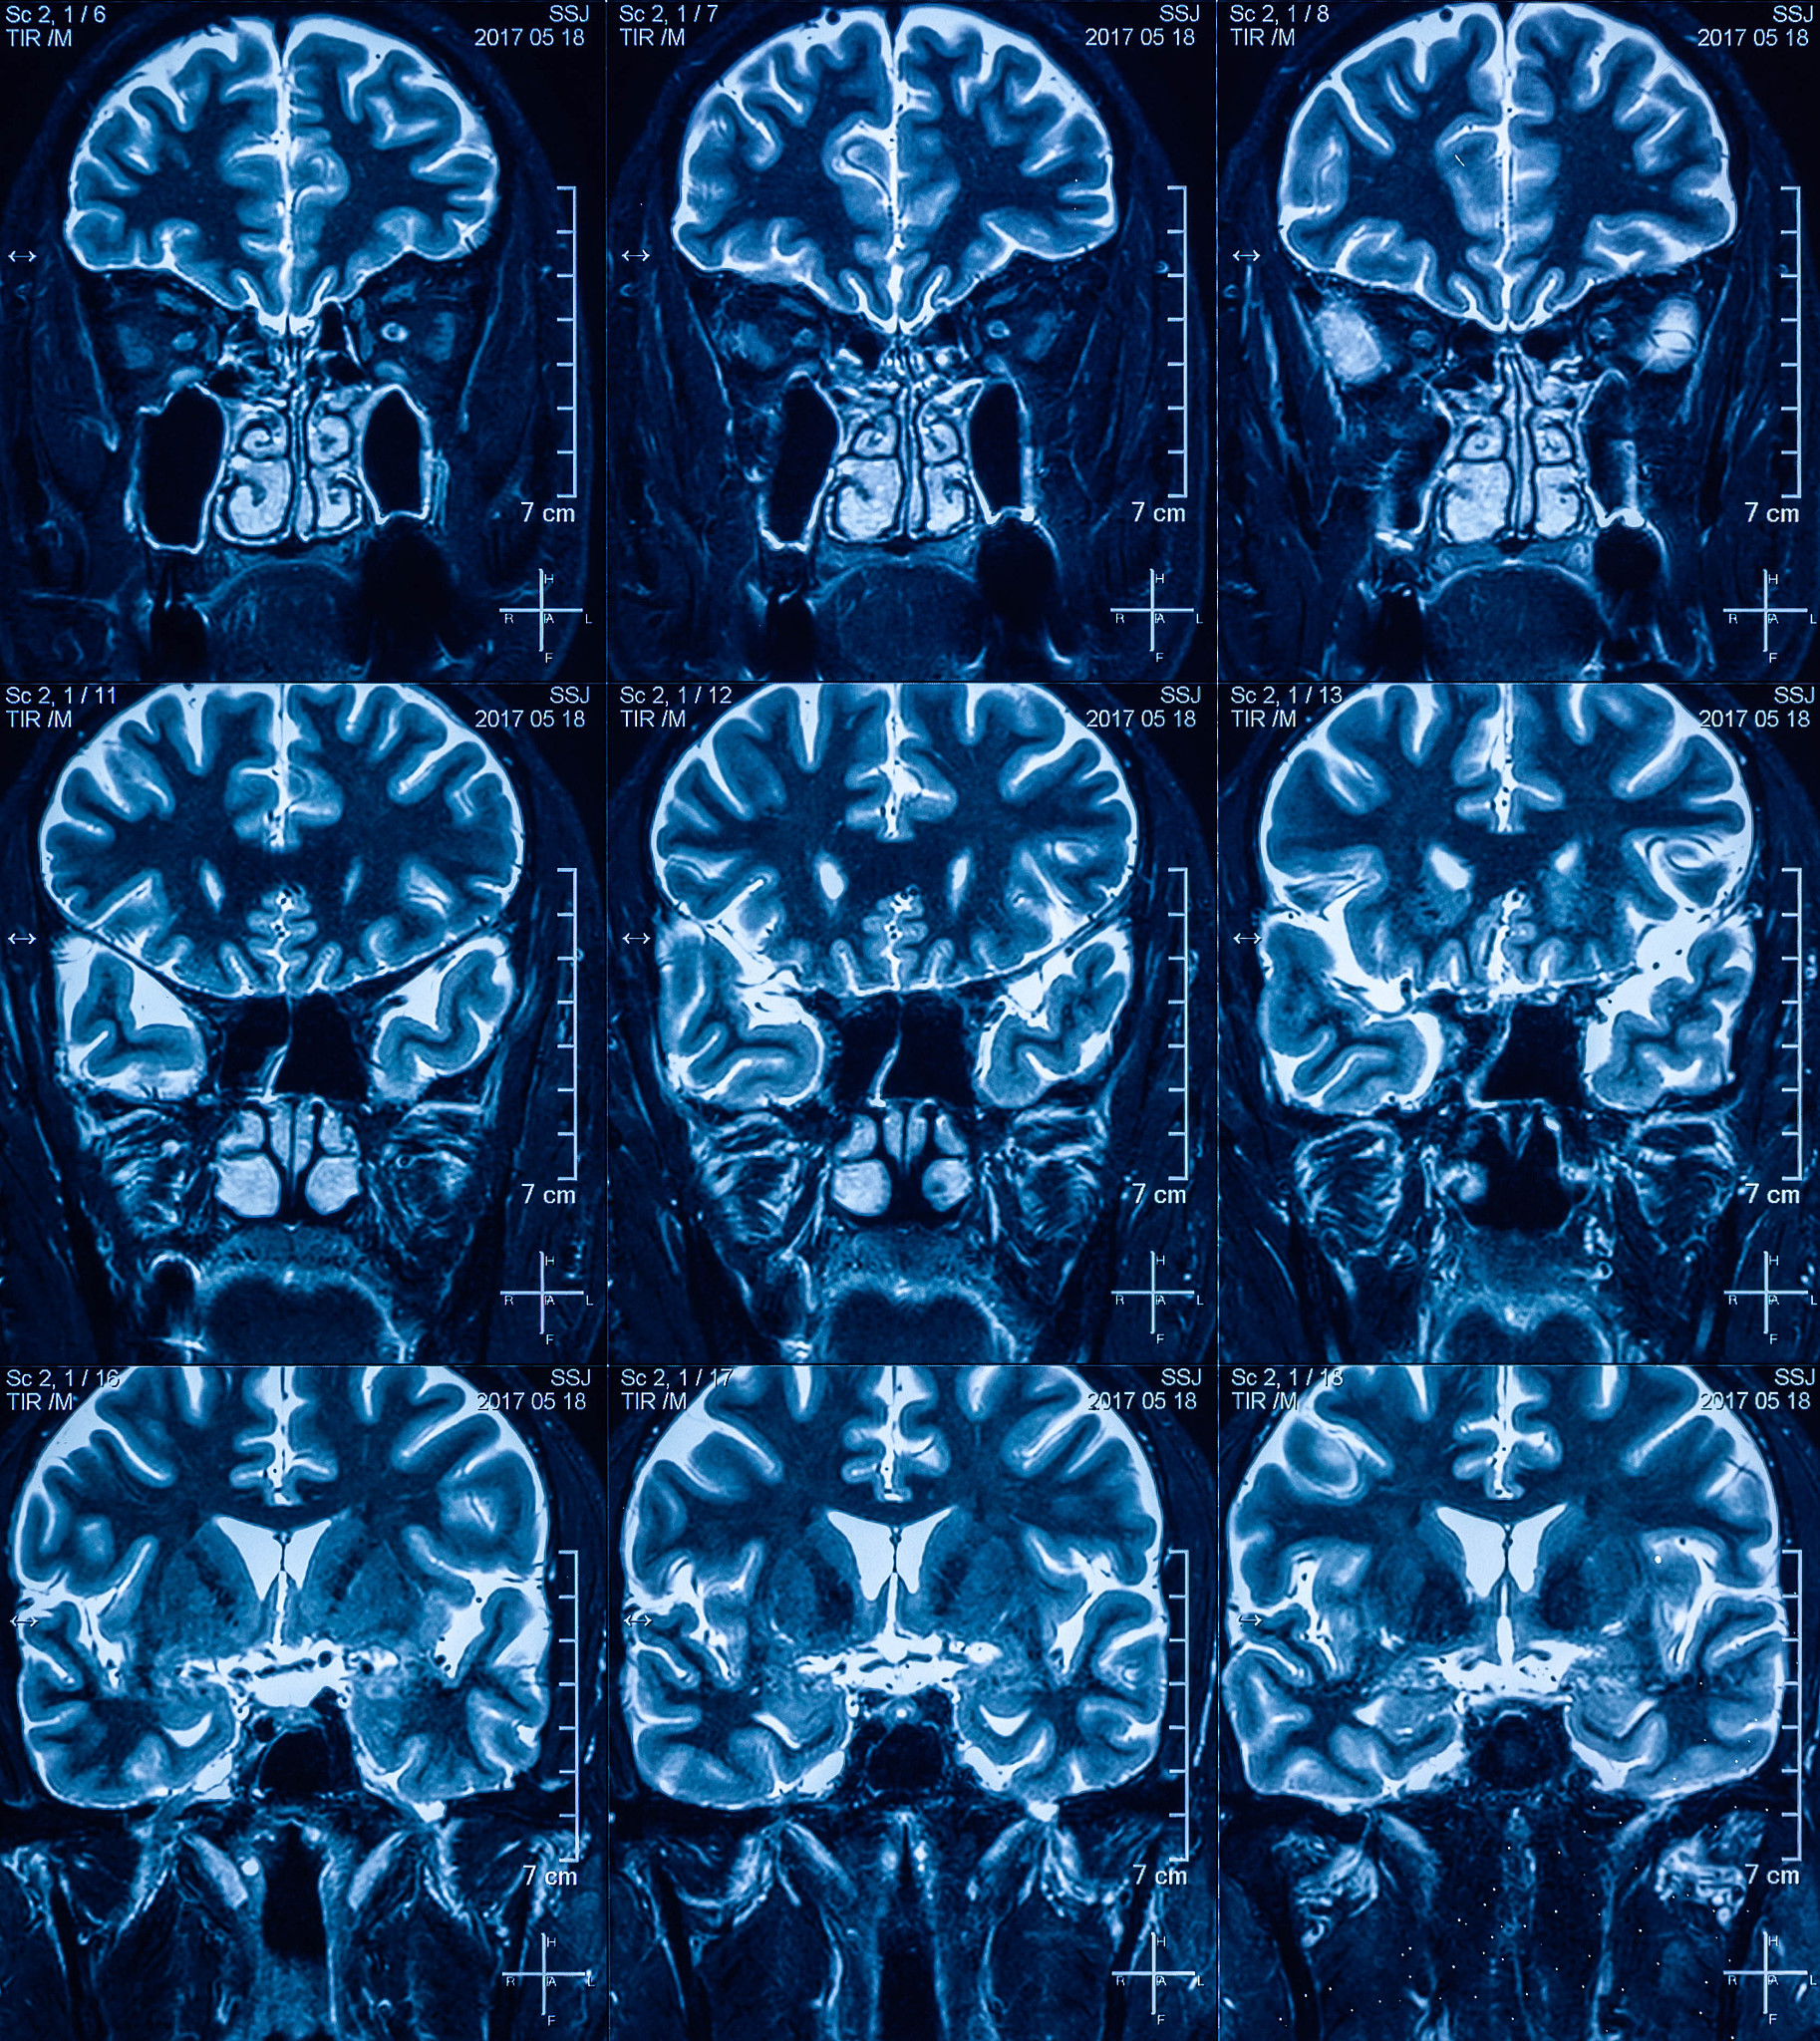

脑脓肿的影像特点如下:

2. MRI:脓肿呈现为T1加权影像低信号、T2加权影像高信号的圆形或椭圆形病灶,周围有水肿和强化环。

3. 脓肿内部可见液化坏死物质和气体。

4. 脓肿位置多在脑组织中央,常见于大脑半球、小脑、脑干和脑室周围。

5. 脓肿周围常有局限性脑水肿和强化环。

6. 脓肿的边缘清晰,与周围正常脑组织分界明显。

脑脓肿影像特点